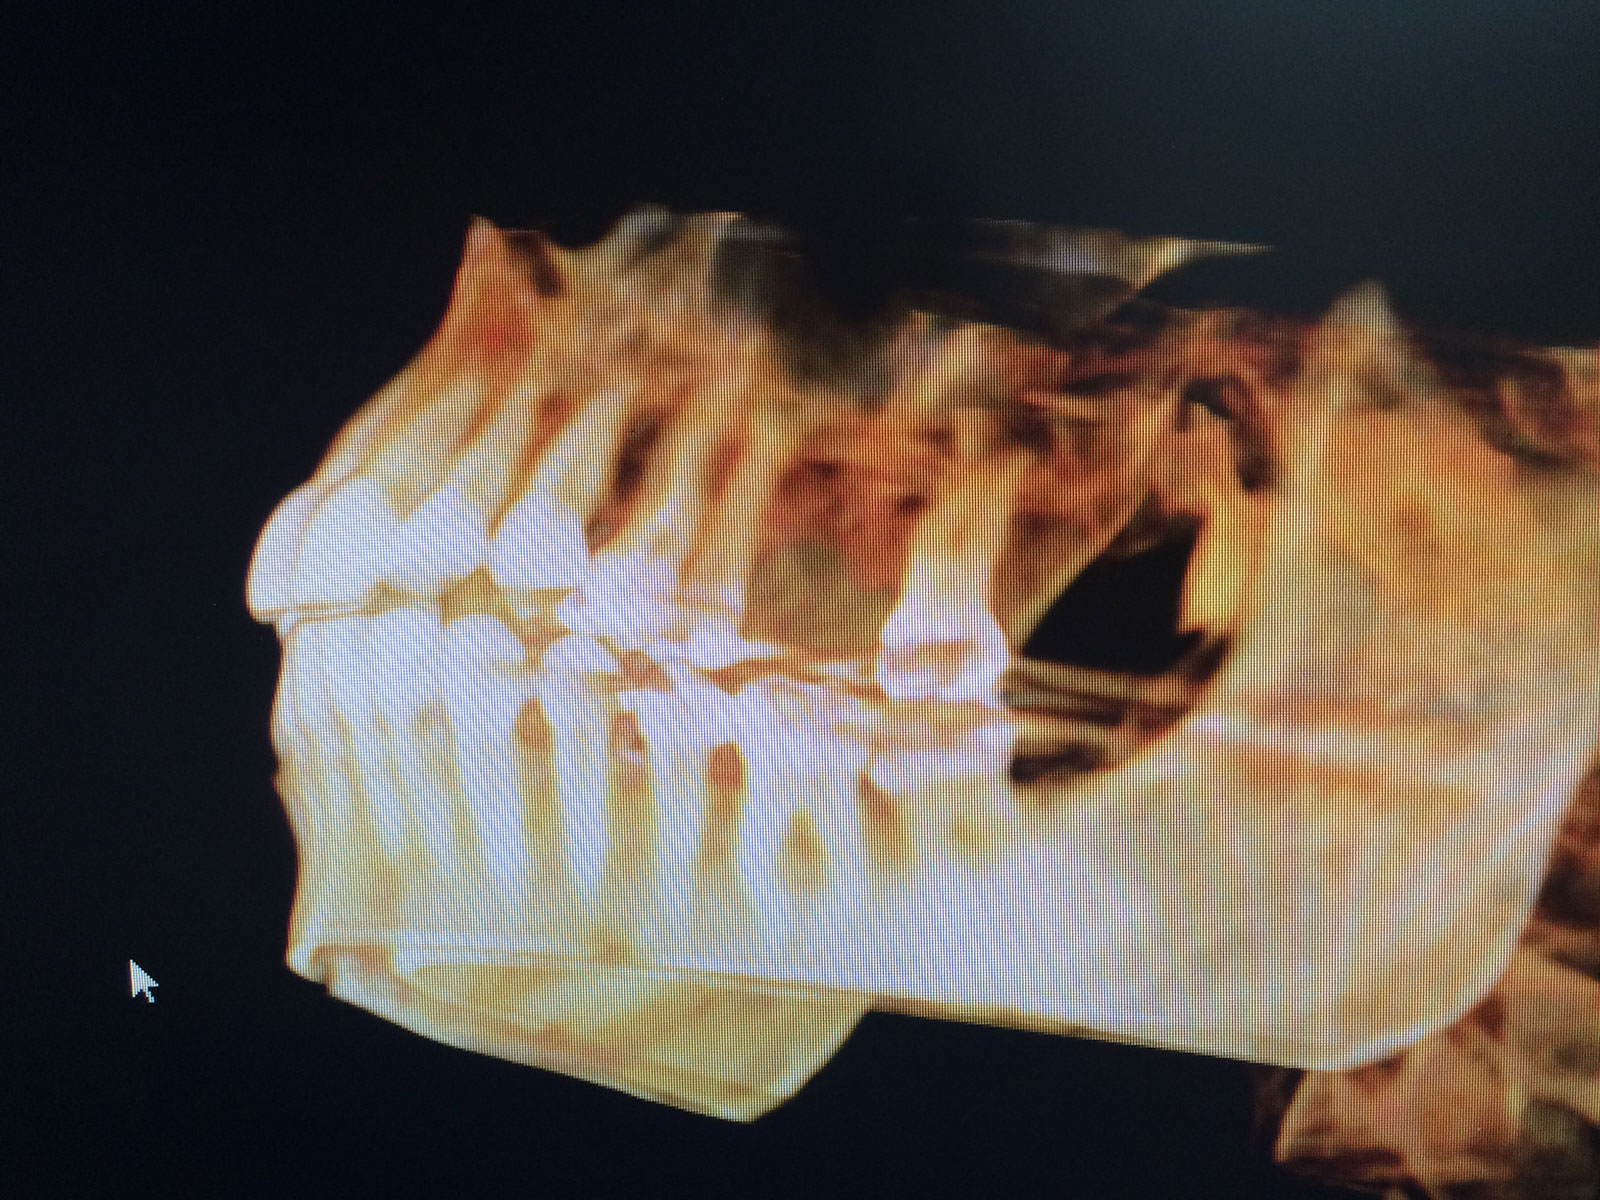

Sinus Grafting Procedures

A sinus grafting procedure, also known as a sinus augmentation, is for patients who have insufficient natural bone in the areas where dental implants are needed. They are long lasting, strong and sturdy, and fit and function like natural teeth. The procedure involves adding bone, either your own natural bone from another part of the body, from a donor or made of processed or synthetic bone material, and placing it below the sinus so that the implants can be placed. After the bone has healed and developed, usually around four to 12 months, the dental implants can be placed.